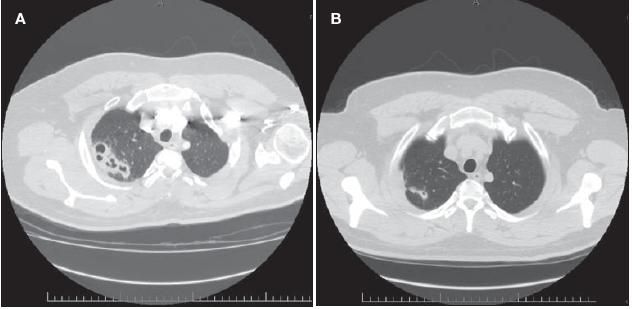

A chest radiograph revealed multiple cavitary lesions in the right upper lobe (Figure 1). A subsequent CT scan of the chest revealed multiple patchy areas of consolidation with cavitation most notable in the right lung (Figure 2A).

Figure 2 – A CT scan of the chest revealed multiple patchy areas of consolidation with cavitation most notable in the right lung (A). After 4 weeks of fluconazole therapy, the patient's cough, hemoptysis, and pleuritic chest pain had resolved, and the CT scan documented significant improvement (B).

After 4 weeks of fluconazole therapy, the patient's cough, hemoptysis, and pleuritic chest pain had resolved. A CT scan of the chestrevealed significant improvement (Figure 2B). Of interest, his Cryptococcus antigen titer had increased to 1:254 after 4 weeks of therapy.